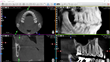

دستگاه تصویربرداری فک و صورت X-MIND TRIUM Pan Ceph